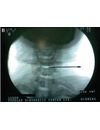

Percutaneous Laser Disc Decompression (PLDD) is a minimally invasive procedure aimed at significantly reducing the patient’s pain and reducing the neurological deficit.